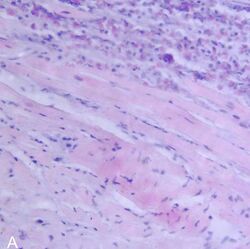

Endomyocardial biopsy specimen with extensive eosinophilic infiltrate involving the endocardium and myocardium (hematoxylin and eosin stain)

The gold standard is the biopsy of the myocardium, in general done in the setting of angiography. A small tissue sample of the endocardium and myocardium is taken and investigated. The cause of the myocarditis can be only identified by a biopsy. Endomyocardial biopsy samples are assessed for histopathology (how the tissue looks like under the microscope): myocardial interstitium may show abundant edema and inflammatory infiltrate, rich in lymphocytes and macrophages. Focal destruction of myocytes explains the myocardial pump failure.[10] In addition samples may be assessed with immunohistochemistry to determine which types of immune cells are involved in the reaction and how they are distributed. Furthermore, PCR and/or RT-PCR may be performed to identify particular viruses. Finally, further diagnostic methods like microRNA assays and gene-expression profile may be performed.[citation needed]